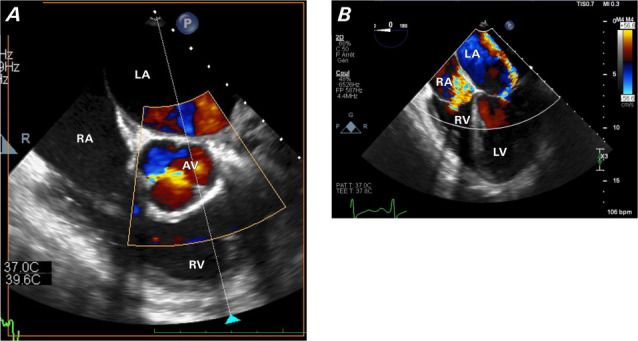

埃尔德海姆-切斯特病是一种罕见的组织细胞增生症,主要影响骨骼系统,但 75% 的病例会出现心血管表现,且预后不良。由于病例较少,该病的演变和治疗尚不确定。因此,报告和分享 Erdheim-Chester 病例非常重要。本报告介绍了一例因埃尔德海姆-切斯特病而患有缩窄性心包炎和二尖瓣反流的年轻患者。

Erdheim-Chester disease is a rare histiocytosis that primarily affects the skeletal system, but cardiovascular manifestations occur in 75% of cases and are associated with a poor prognosis. Given the small number of cases, the evolution and management of the disease are uncertain. Therefore, it is important to report and share Erdheim-Chester cases. This report presents the case of a young patient with constrictive pericarditis and mitral valve regurgitation resulting from Erdheim-Chester disease.